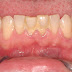

Mảng bám vôi răng*

Mảng bám trên răng là những mảnh vụ thức ăn tích tụ lại trên bề mặt răng, dưới nướu sau khi ban ăn uống. Nếu các mảng bám trên răng này không được làm sạch, lâu ngày sẽ bị vôi hóa, hình thành cao răng bám cứng chắc vào bề mặt răng.

Ngoài ra, nếu không áp dụng các phương pháp làm sạch mảng bám trên răng thì sẽ gây ra hiện tượng răng bị ố vàng, xỉn đen, ảnh hưởng đến thẩm mỹ. Mảng bám còn là nơi trú ngụ của vi khuẩn dẫn đến các bệnh lý răng miệng nguy hiểm.